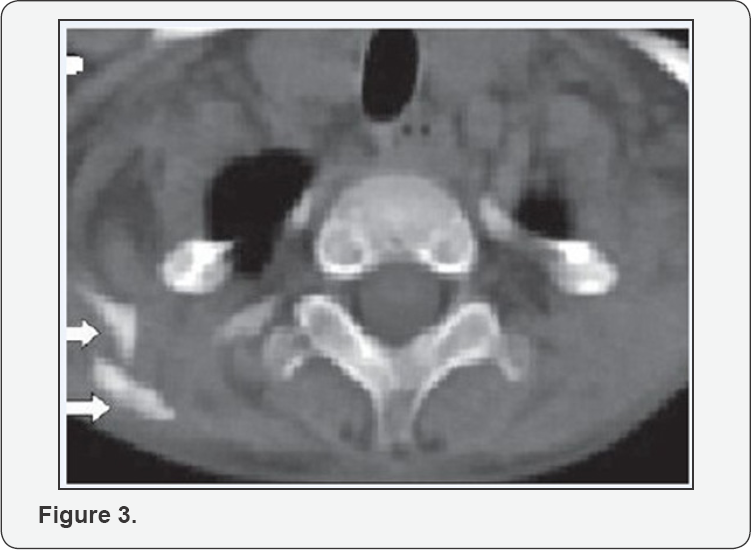

The radiological skeletal survey revealed extensive heterotopic ossification in neck, thoracic walls, back, upper limbs and hips with bone deformities (Figure 2). CT thorax showed multiple plaque-like calcifications involving the pectoralis major and para-spinal muscles (Figure 3). Diagnosis of FOP was strongly considered. Blood samples of both the parents and child were collected for sequencing the activing receptor IA (ACVR1) gene. A heterozygous mutation(617 G>A; q.R206H), which is the most common mutation reported to be associated with FOP, was detected in the child confirming the diagnosis As there were no acute flare-ups, no NSAID's or steroids were given. The child was given graded physiotherapy and parents were explained the nature of ailment with precautions to prevent trauma (particularly iatrogenic injury from intra-muscular injections, biopsies, and surgery) and trivial injuries inflicted during playful activities.

CT scan

CT demonstrates fascia plane edema and swelling and mesenchymal mass like lesion in the muscle that moderately enhances with IV contrast. In late disease after ossification and calcification